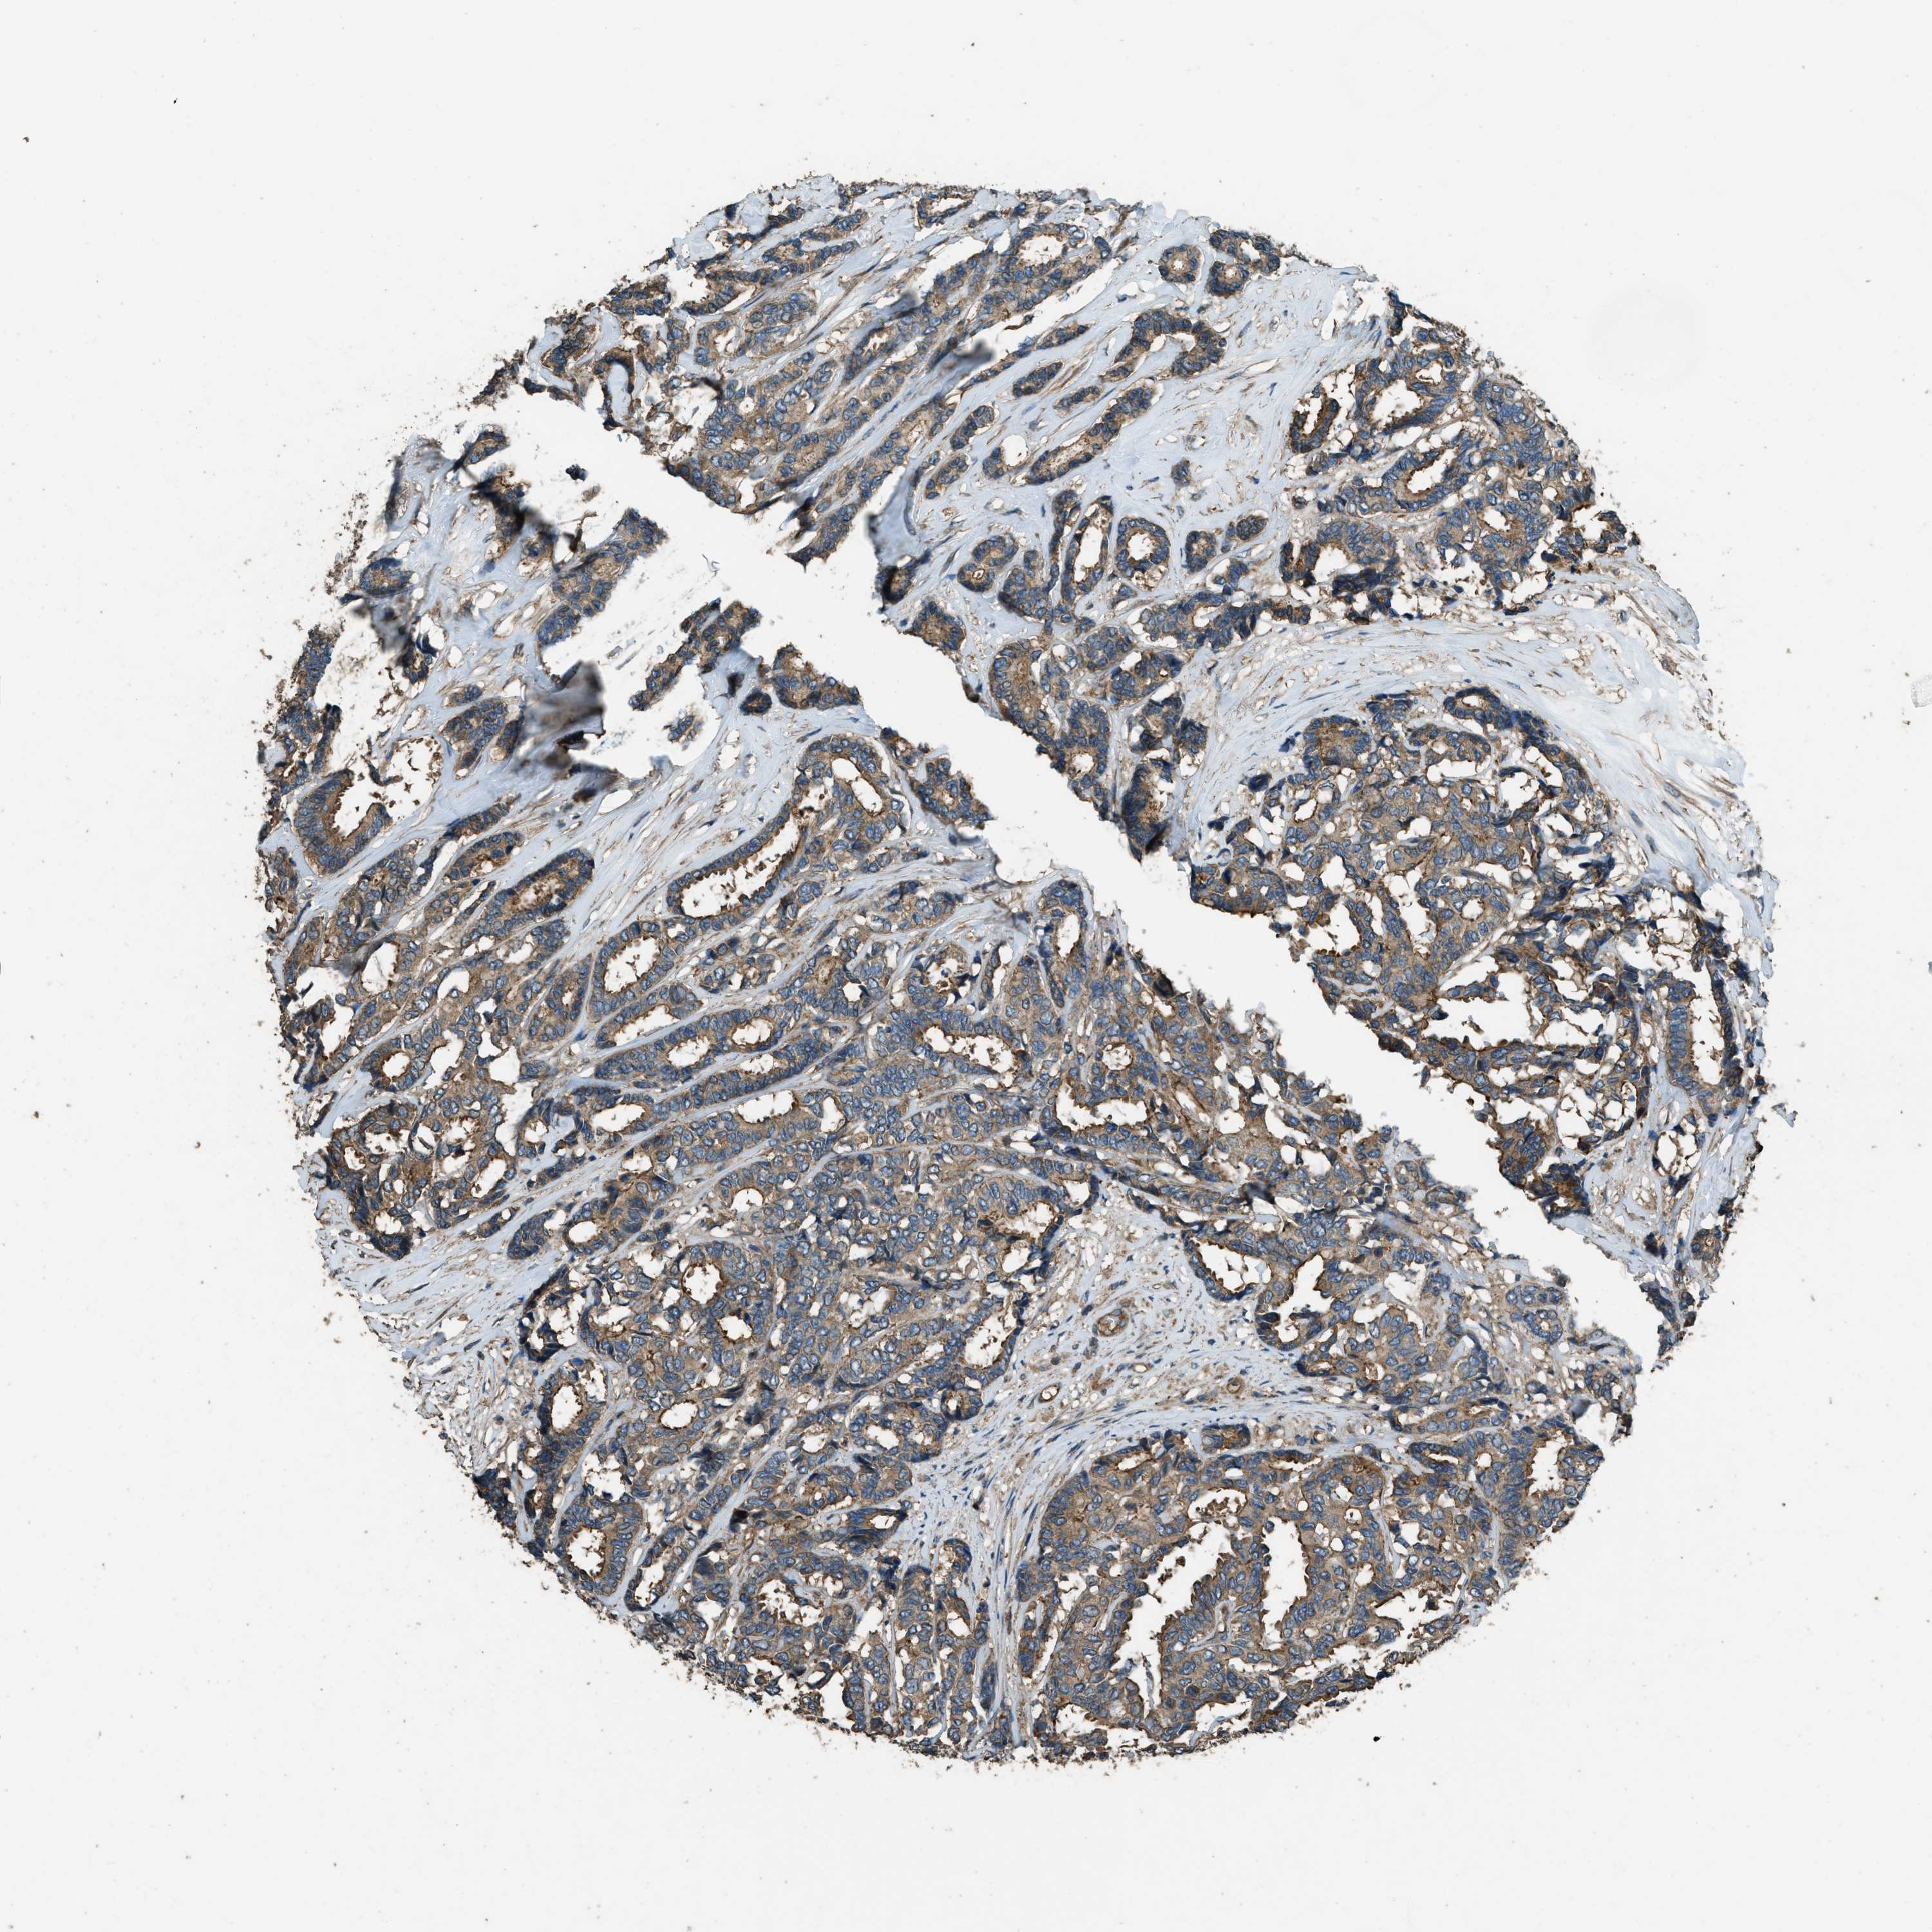

CANCER BREAST CANCER Show tissue menu

BRCA TCGA BRCA VALIDATION PROTEIN EXPRESSION

MARS1 is potential prognostic, high expression is unfavorable in Breast Invasive Carcinoma (TCGA)